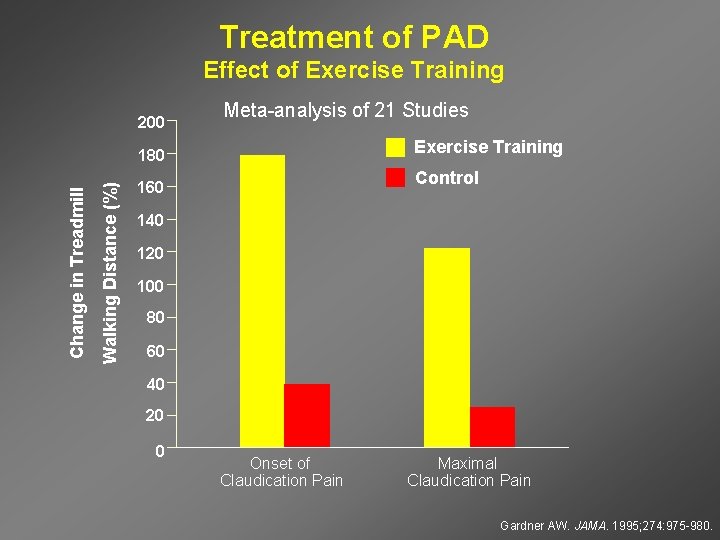

Treatment of PAD Effect of Exercise Training 200 Meta-analysis of 21 Studies Exercise Training Walking Distance (%) Change in Treadmill 180 Control 160 140 120 100 80 60 40 20 0 Onset of Claudication Pain Maximal Claudication Pain Gardner AW. JAMA. 1995; 274: 975 -980.